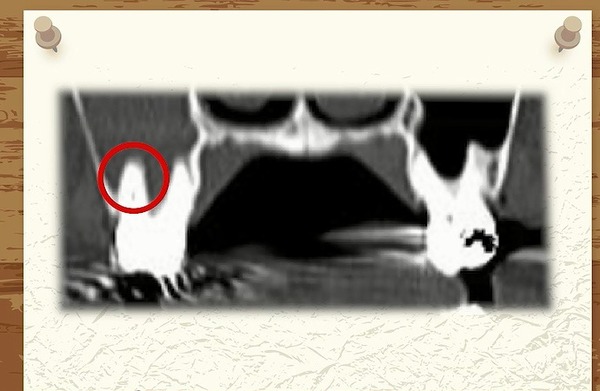

レントゲン写真は硬いものが白くうつります。

↑

ここに白い線がはっきりくっきりと

うつっています。

ここには

硬い骨

太い骨

があるのです。

ではこの硬い骨、太い骨は

どういう役目があるのか?

この硬い骨と太い骨は

口の部屋と鼻の部屋が混ざらないように

仕切っている壁なんですね。

口側には

歯の頭と歯の根っこと

その根っこを支える骨が

あります。

硬い骨と根っこの間には隙間(骨)があります。

これは

鼻の部屋を分けている

硬い骨です。

そして反対側です。

左側のはっきりくっきりした線に比べると

右側は

途中までははっきりした線がありますが

しかし赤丸の一番大きい歯のところは

はっきりと線が見えません。

人間の体は

だいたい左右対象的ですから

本来の鼻のラインはどこか?

ちょっと右と左でうつり方が違いますね。

本来ならば硬い骨よりも

口側に

歯の根っこや骨が入っていないといけません。

もちろんCTなどで立体的に見れば

そうなのかもしれませんが

平面のレントゲン写真では重なってしまっていて

そのようにうつってくることもあります。